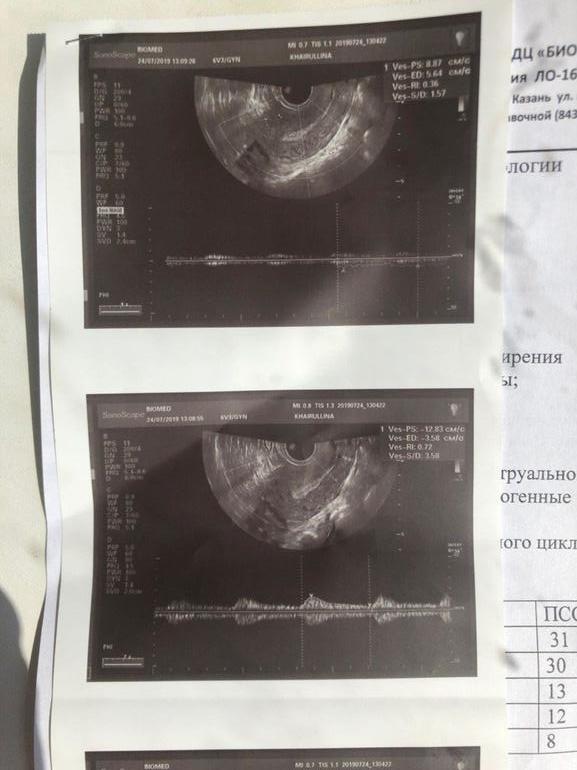

сегодня у другого врача в другой клинике 7,8......(((ну и сам доплер, помогите пожалуйста, разобраться , узист делала молча, в заключении ничего нет

1.Правая маточная артерия 2.Левая маточная артерия 3.Аркуатные артерии 4.Радиальные артерии 5.Базальные артерии 6.Спиральные артерии Наиболее важные для имплантации и вынашивания на первоначальном этапе и наиболее часто страдающие от ХЭ артерии - это Базальные и Спиральные. Пока кровотока в них нет, или он снижен, беременность может продолжать срываться/замирать. Правая и левая маточные артерии не столь важны для вынашивания на первоначальном этапе. Однако обычно с ними как раз у большинства все в порядке. Во время измерения сосудов, на экране монитора будут ловить пульсацию в каждой артерии, и вы будете видеть примерно такую картинку: УЗИст же будет замерять эту пульсацию. Это правильное исследование. Часто доплером называют еще вот этот "режим цветных пятен": Это тоже кровотоки в режиме доплера. Многие УЗИсты просто смотрят именно этот режим доплера и сообщают вам, что все хорошо. Не ведитесь! Информации о скорости кровотоков такое исследование не несет. Когда делать доплер? Доплер сосудов матки необходимо делать на 5-7 ДПО (день после овуляции). Нормы доплера есть на любой день цикла, и в принципе узнать о плохом кровотоке вы можете, сходив на доплер в любой ДЦ. На 5-7 ДПО его смотрят за тем, что это время приходится на окно имплантации при возможной беременности. Какой нужно получить результат от УЗИста на руки? Правильный результат доплера выглядит как все перечисленные выше артерии с количественными показателями, включая самый популярный - Индекс Резистентности (ИР). (Или только с ИР, этого достаточно). Если по-английски, то RI. Данный индекс характеризует скорость кровотока и имеет свои нормы. Резистентность - это сопротивление, то есть чем ИР ниже, тем лучше, тем быстрее кровоток, а значит лучше для беременности. То есть когда говорят о высокорезистентном кровотоке, имеют ввиду, что кровоток плохой. Соответственно, на руки вам должны выдать результат ИР во всех шести артериях матки и вывод УЗИста о состоянии кровотока. Каковы нормы доплера? Нормы ИР для второй фазы цикла: